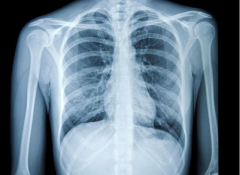

2. 试管为什么要拍胸片?一文为你科普!

试管为什么要拍胸片?一文为你科普!

对于做试管的患者来讲,拍胸片主要的目的就是为了排除有无出现肺部疾病,比如肺结核、肺炎、肺部肿瘤等各种疾病,这是一项比较常规的身体检测。夫妻双方都需要进行胸片,检查观